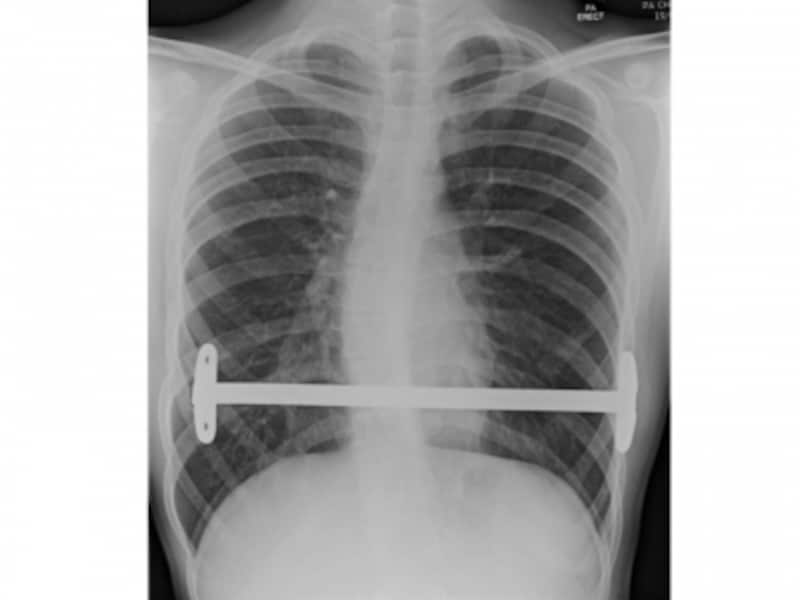

術後のX線像です。

術後の胸部単純X線像。